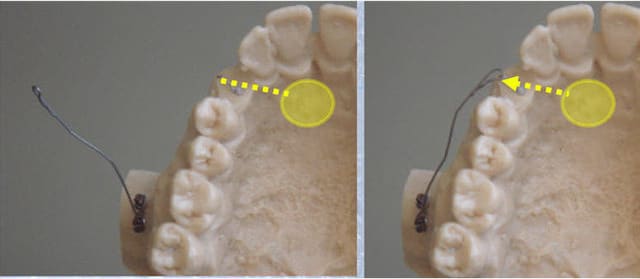

Tout sera fait jusqu'au bout par le même système, il ne sera nécessaire de placer une gouttière de finition.

La suite : on a dégagé et collé un bouton sur sa couronne en même temps qu'on a viré la 53..

Et maintenant, qu'est-ce qu'on fait ?

Il nous faut des points d'appui pour la tracter en vestibulaire !

Arnaud Go propose une "plaque osseuse" ou un "implant d'ancrage"..

Pourquoi pas, mais à quoi ça ressemble ?

Où est-ce qu'on le (les) met ?

Qu'est-ce qui est le plus simple et à ma portée, sachant que je suis orthodontiste et non chirurgien maxillo-facial, et que c'est moi qui réalise ce traitement de "A" jusqu'à "Z", y compris sa partie chirurgicale ?

Tu as bien vu. Pourquoi appelles-tu ça "le coup" du CT8-1 ?

Je pense vraiment que c'est le meilleur système actuel pour tracter les canines incluses, qu'il devrait être généralisé et diffusé un maximum.

Et comme beaucoup ne connaissent pas, il est bon de temps en temps de relancer la machine..

Et puis il y a aussi, pour ce cas-ci, des astuces de correction que je ne crois pas avoir déjà présentées ici.

Encore 2 images démonstratives.